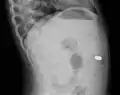

Gastrointestinal tract

One of the most common locations for a foreign body is the alimentary tract.

It is possible for foreign bodies to enter the tract from the mouth or rectum.